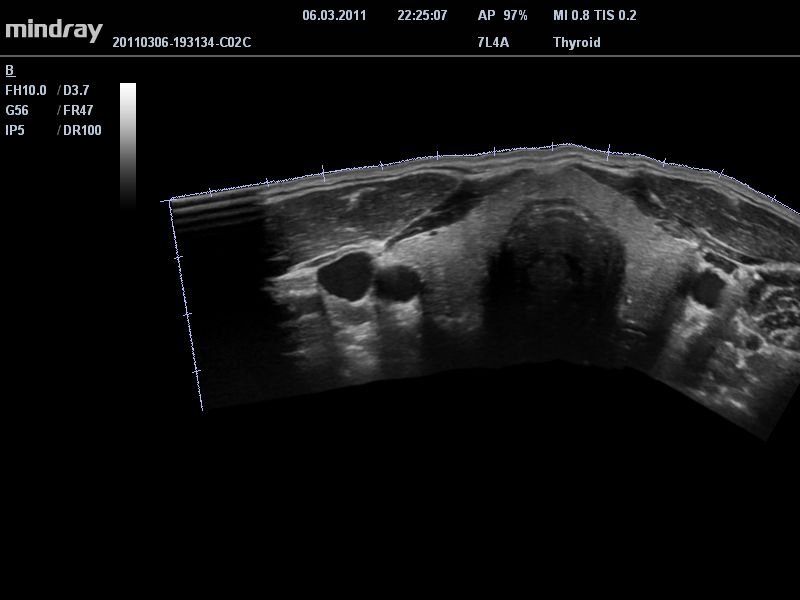

Ультразвуковая система Mindray DC-T6 – это инновационный аппарат для проведения высокого уровня диагностики с качественной визуализацией и широким спектром применения. Платформа рекомендована для использования в коммерчески многопрофильных медицинских учреждениях и государственных лечебных клиниках.

Система сочетает в удобном и компактном корпусе не только традиционные возможности современного УЗИ-сканера, но и инновационные технологии, повышающие точности диагностики состояния пациентов.

• Режимы сканирования: B/M/CFM/PDI/Направленный PDI/PW, HPRF, Тканевая гармоника, М- и цветной М-режим.

• Просмотр изображения в режиме iScape™: панорамирование изображения в реальном времени.